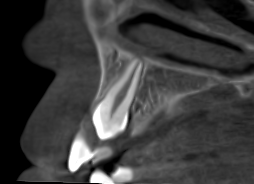

Los restos radiculares ocultos son una causa frecuente de molestias persistentes tras una extracción dental. En muchos casos, estos fragmentos

Las infecciones dentales recurrentes son una causa frecuente de consulta tanto en odontología general como en cirugía oral. Pacientes que

Las extracciones complejas, especialmente de terceros molares inferiores, suponen un reto quirúrgico cuando existe cercanía entre las raíces dentarias y

El CBCT (Tomografía Computarizada de Haz Cónico) es una de las herramientas diagnósticas más importantes en la odontología actual. Su